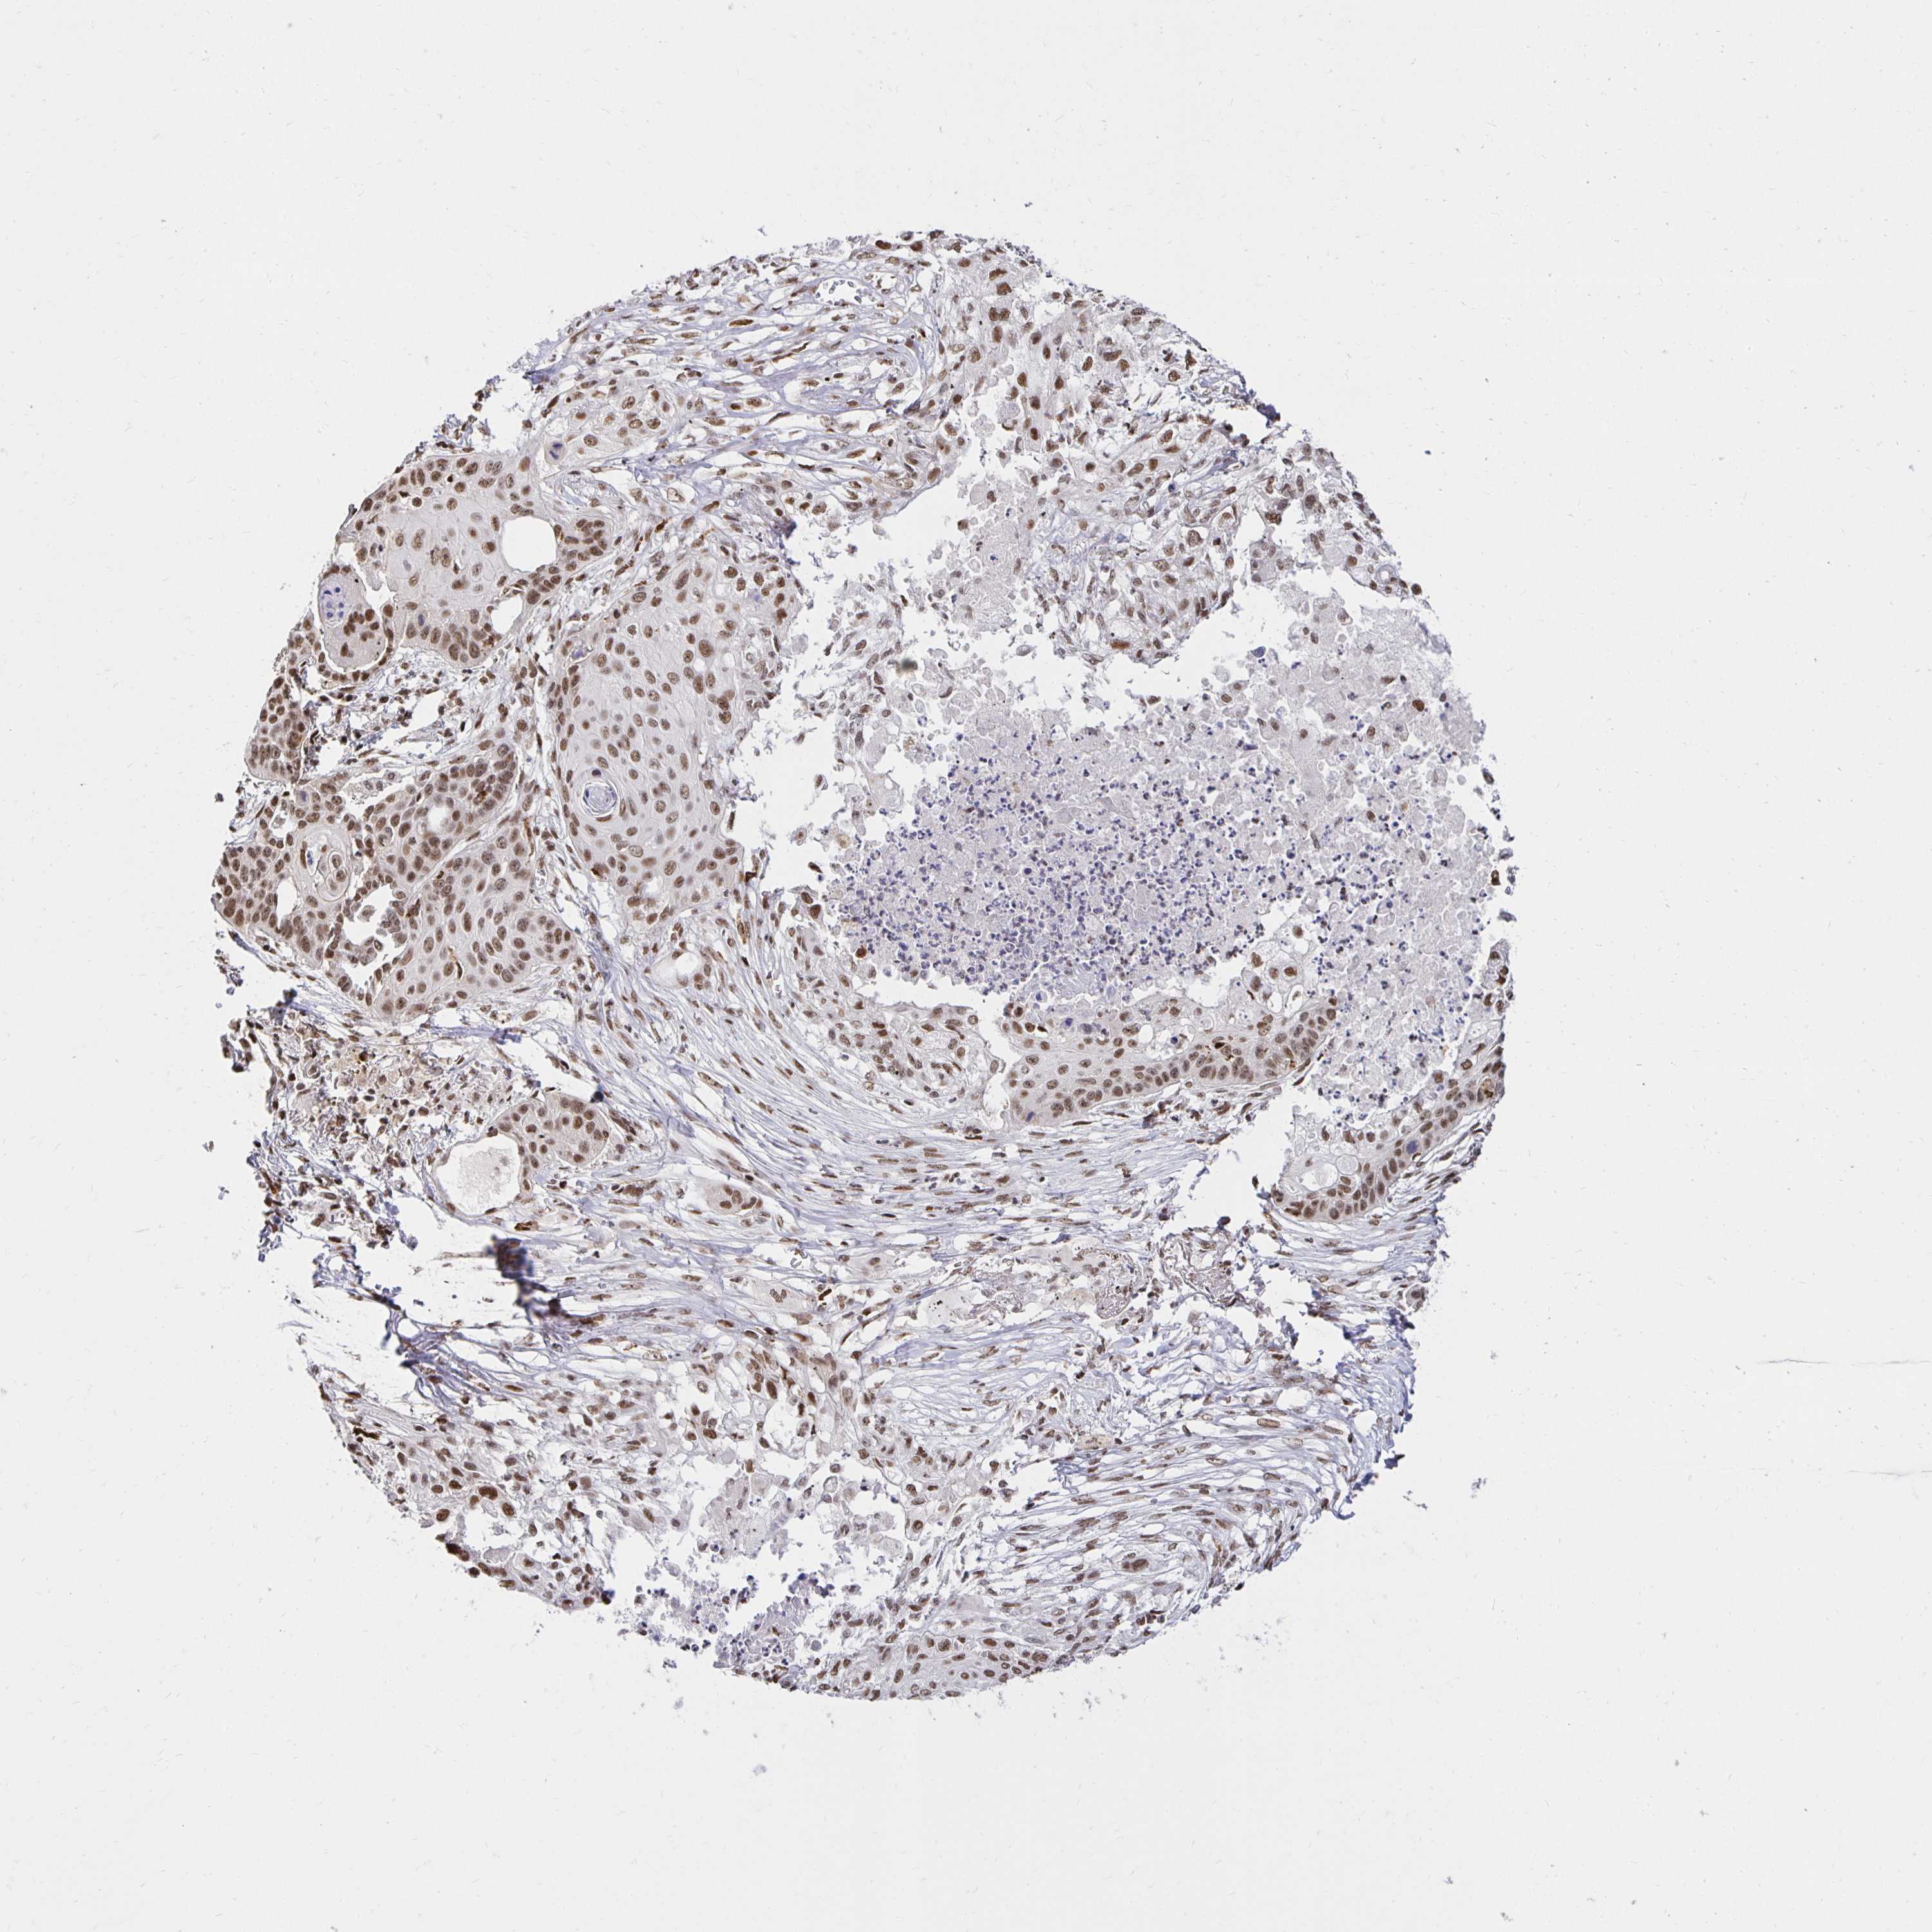

CANCER LUNG CANCER Show tissue menu